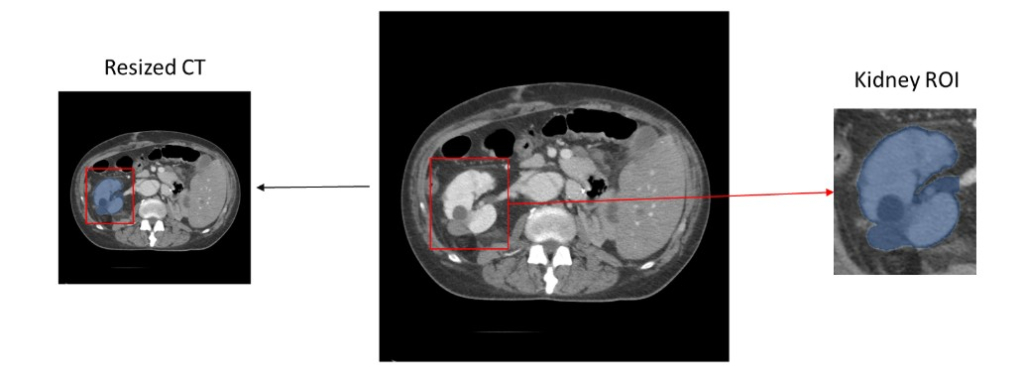

MCL Research on Medical Image Classification

We propose the development of a high-efficiency foundation model tailored for the MedMNIST v2 benchmark, utilizing a novel architecture based on Multi-Resolution [...]